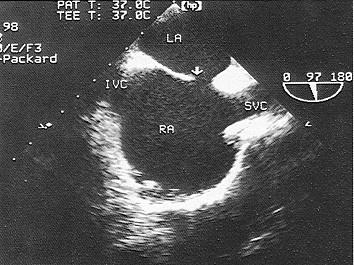

问题 该食管超声心动图显示图像为?(?)

选项 A.房间隔缺损(上腔型) B.房间隔缺损(下腔型) C.房间隔缺损(中央型) D.房间隔缺损(混合型) E.冠状静脉窦扩张

答案 A